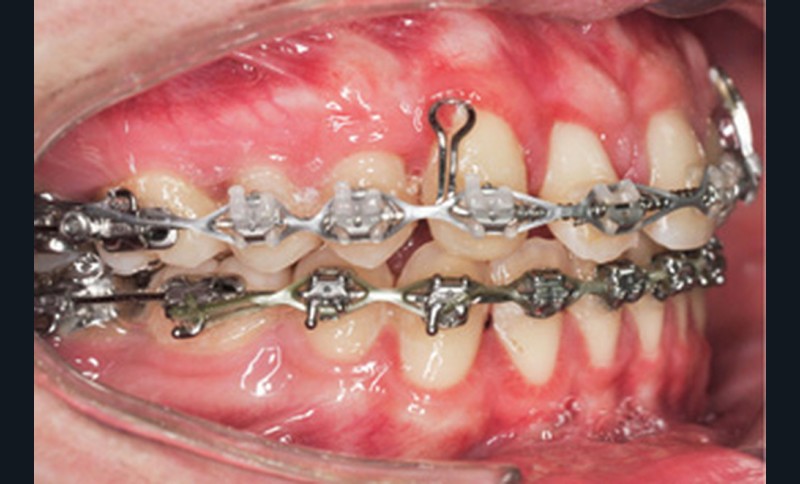

Le nivellement a nécessité trois arcs en Copper-NiTi (.014/.016 x .022/.019 x .025). Les mécaniques intra arcades (fermeture des espaces) et interarcades (élastiques de tractions intermaxillaires de classe II) ont été effectuées sur des arcs en acier .019 x .025. La gestion asymétrique de la mécanique de rétraction maxillaire a débuté par le recul de 23 (ancrage postérieur dentaire + élastiques intermaxillaires de classe II). Une fois 23 symétrisée avec 14 (substituant la 13), le centrage de 12 a débuté pour le remplacement de la 11. La rétraction du groupe antérieur par un arc à boucles de rétraction en acier .019 x .025 permet d’ajuster le torque radiculo-palatin pour contrer le rabbiting antérieur (fig. 2a-c).